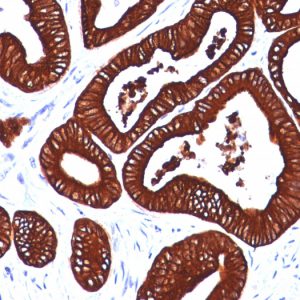

Cytokeratin 19 (CK19), encoded by the KRT19 gene located on chromosome 17q21.2, is a type I intermediate filament protein. It consists of 400 amino acids and has a molecular weight of approximately 44 kDa. CK19 undergoes various post-translational modifications, including phosphorylation, glycosylation, and the formation of disulfide bonds, which can modulate its stability, localization, and function within cells. CK19 is primarily an intracellular protein, serving as a structural component of the cytoskeleton.

It is expressed in a wide range of tissues and organs, including the liver, gastrointestinal tract, mammary glands, and bile ducts. Additionally, CK19 is involved in various cellular processes, including cell migration, signaling, and apoptosis regulation. Various factors, including developmental signals, hormonal influences, and tissue-specific transcription factors, regulate the expression of CK19 to ensure proper tissue homeostasis and function. Dysregulation of CK19 expression or mutations in the KRT19 gene have been associated with various health conditions and diseases. For example, mutations in CK19 have been linked to liver diseases, such as primary biliary cholangitis (PBC) and liver cirrhosis. CK19 expression has also been utilized as a marker of specific cell types (e.g., pancreatic stem cells ) or disease states in diagnostic pathology.

Previous studies have shown that CK19 expression in tissue samples can provide valuable diagnostic and prognostic information in assessing various cancers, particularly in malignancies affecting epithelial tissues. For example, In breast cancer, CK19 expression is frequently assessed to subtype tumors and distinguish between different histological types. Its presence or absence can help pathologists classify tumors into different molecular subtypes, affecting treatment decisions and patient prognosis. Similarly, in pancreatic cancer, CK19 expression has been found to be associated with tumor aggressiveness and poorer patient outcomes. Detection of CK19-positive tumor cells in pancreatic tissue samples can aid in diagnosing pancreatic adenocarcinoma, one of the most common and lethal forms of pancreatic cancer. Furthermore, in cholangiocarcinoma (bile duct cancer), CK19 expression is often used as a diagnostic marker to differentiate between malignant and benign biliary lesions.

NeoBiotechnologies offers a variety of antibodies against KRT19 that have been validated for flow cytometry, immunofluorescence, immunohistochemistry, and Western blotting. Additionally, we hold exclusive rights to KRT19 antibodies available for licensing or collaboration [https://www.neobiotechnologies.com/shop/?s=KRT19].